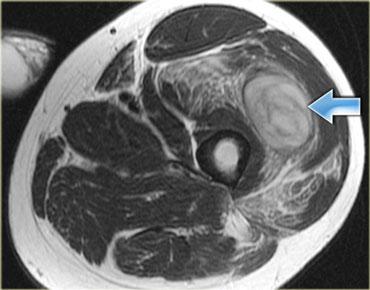

Bên trái là cơ thẳng đùi bị tổn thương.

Các hình ảnh cho thấy tổn thương mức độ vừa, với sự biến dạng cấu trúc và một ổ tụ dịch (mũi tên).

Lưu ý phù nề tại chỗ nối cơ-gân dạng hai lông chim.